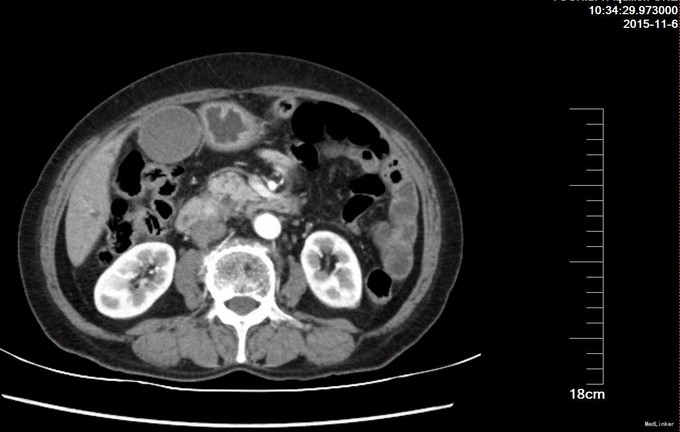

查体: T36.6℃,P78次/分,R16次/分,BP135/75mmHg,全身皮肤及巩膜黄染,无腹壁静脉曲张,未见胃肠型及蠕动波,腹部触之软,无压痛,无反跳痛及肌紧张,肝脾肋下未触及,Murphy's征(-),肝脾肾区无叩痛,移动性浊音(-),肠鸣音4次/分. 辅查: 肝功能化验总胆红素明显升高,以直接胆红素升高为主。 CT提示肝脏大小形态正常,肝内见小囊状不强化灶。肝内外胆管普遍明显扩张,胆总管管径约2.0cm。胆囊增大,肝门部胆管内见高密度结节影,约1.1cm;胰管扩张,约0.8cm,壶腹部见一软组织密度结节影,约1.6cm×1.4cm,增强扫描强化明显不均匀。 EUS:超声探头置于十二指肠球部扫查,见胰管扩张,直径约8mm,胆总管扩张,直径约23mm,胆总管末端见一低回声肿块,内部回声不均匀,大小约23x18mm。